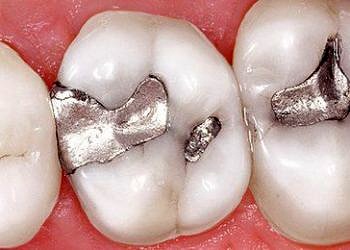

Amalgam dolgu (civalı) oldukça yaygın kullanılan bir diş dolgusu türüdür. Ancak son zamanlara sık sık tartışılıyor ve amalgam dolguların (gümüş dolgu)...